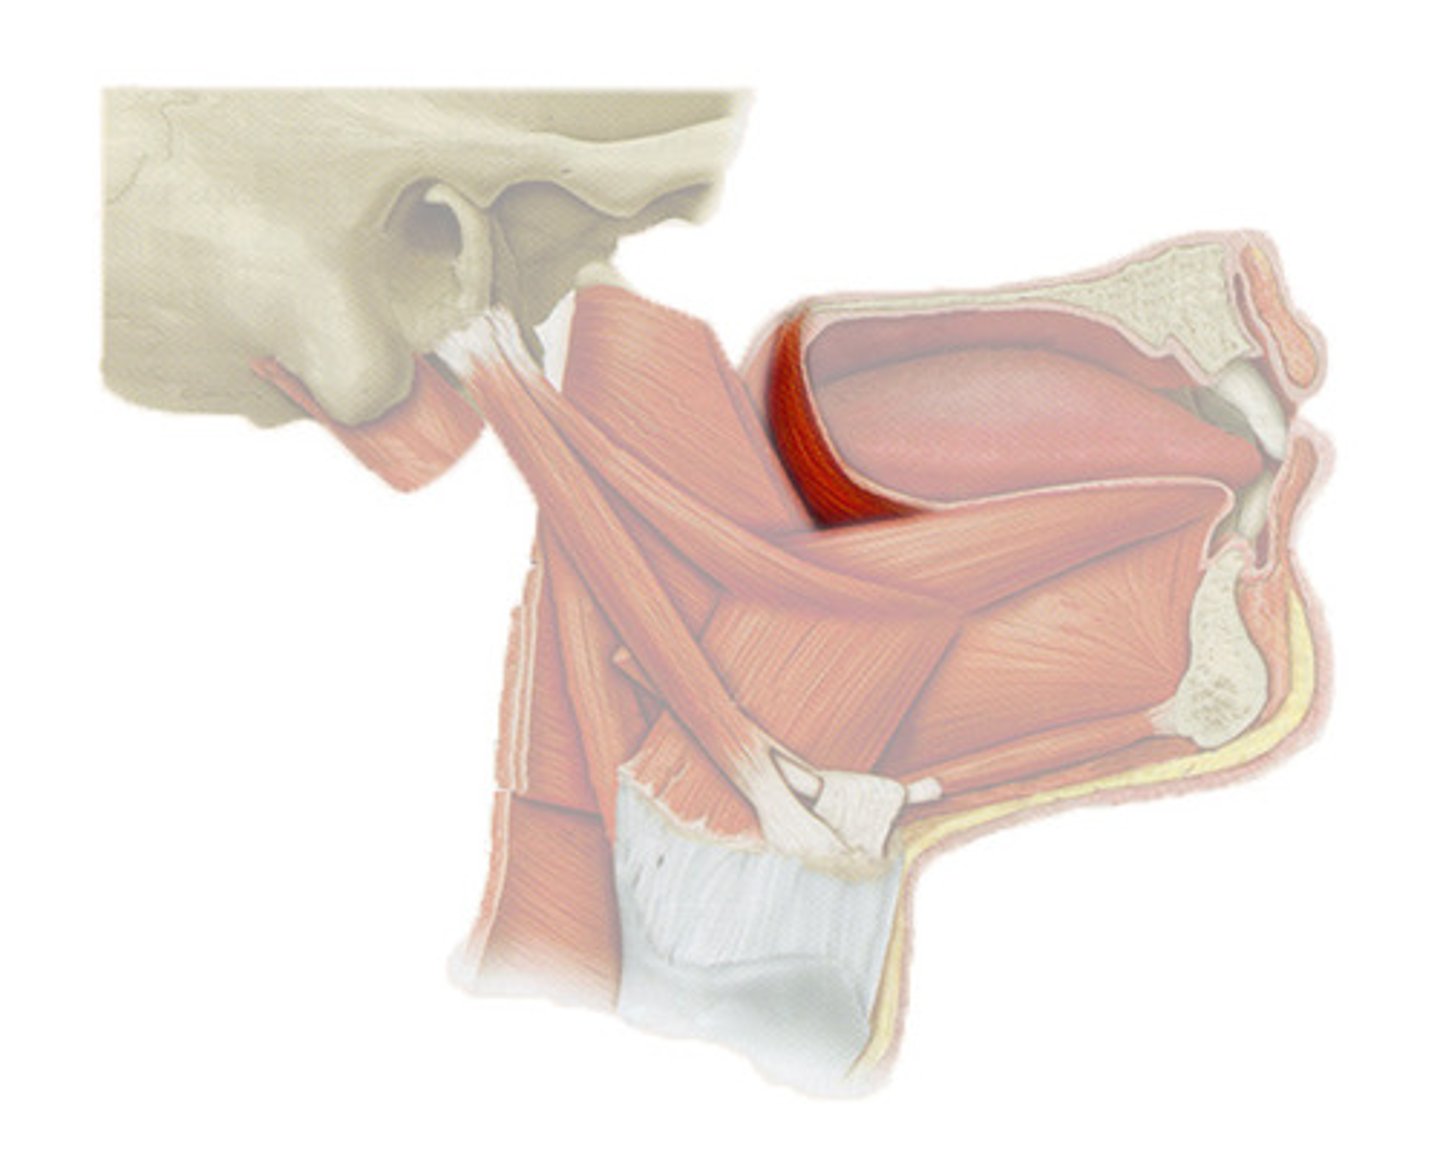

Digastric

Stretches between the mastoid process of the cranium to the mandible at the chin, and part-way between, it becomes a tendon which passes through a tendinous pulley attached to the hyoid bone

Mylohyoid

A paired muscle running from the mandible to the hyoid bone, forming the floor of the oral cavity of the mouth

Stylohyoid

A slender muscle, lying anterior and superior of the posterior belly of the digastric muscle. It shares this muscle's innervation by the facial nerve, and functions to draw the hyoid bone backwards and elevate the tongue. Its origin is the styloid process of the temporal bone.

Sternohyoid

A thin, narrow muscle attaching the hyoid bone to the sternum, one of the paired strap muscles of the infrahyoid muscles serving to depress the hyoid bone

Thyrohyoid

A small skeletal muscle on the neck which depresses the hyoid and elevates the larynx

Sternothyroid

Lies underneath the sternohyoid muscle

Omohyoid

A muscle that depresses the hyoid. It is located in the front of the neck and consists of two bellies separated by an intermediate tendon.

Palatoglossus

Extrinsic muscle of the tongue

Genioglossus

The fan-shaped extrinsic tongue muscle that forms the majority of the body of the tongue